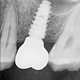

Dental Implants in Kolkata: Everything You Need to Know Before Getting One

Missing a tooth can affect your smile, confidence, chewing ability, and even the shape of your face. For many people in Garfa, Jadavpur, Jodhpur Park, Kasba, Santoshpur and nearby South Kolkata, dental implants have become the most trusted long-term solution. If you are considering replacing a missing tooth, this guide will help you understand everything about dental implants — from procedure to cost to safety.

At SurgiDent Oral & Maxillofacial Clinic, Garfa, we specialize in painless and predictable implant procedures performed by trained oral surgeons, ensuring safe and natural-looking results.